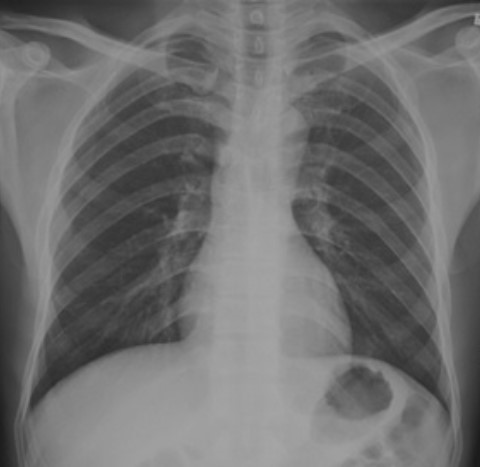

5.根據(jù)下圖請(qǐng)做出正確診斷

A.正常胸片

B.肺門淋巴結(jié)腫大

C.肺炎

D.主動(dòng)脈型心(靴型心)

答案提示:【該題針對(duì)“ X線-正常胸片 ”知識(shí)點(diǎn)進(jìn)行考核】